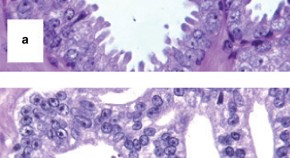

Patients with bladder cancer have a substantially increased risk of prostate cancer, compared with that of the general male population, and a diagnosis of concomitant prostate cancer can contribute to inferior outcomes, particularly in patients with muscle-invasive bladder cancer. Here, the authors describe the outcomes of such patients, in addition to the optimal treatment and management strategies and future research needs.